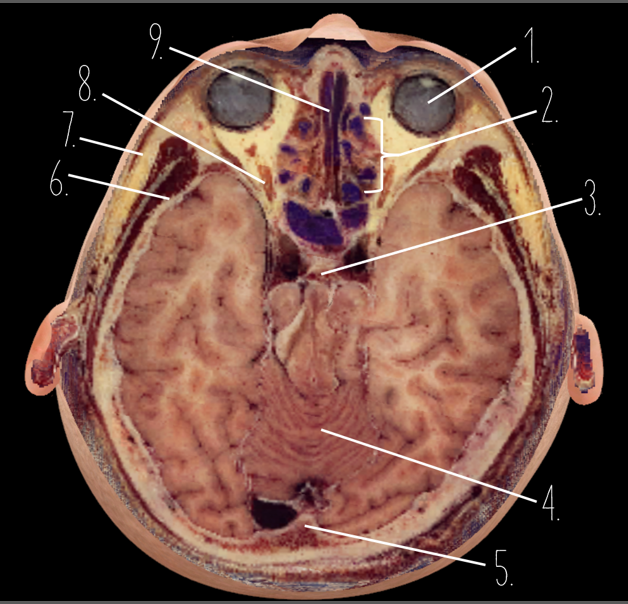

1?

Globe of Eye

2?

Ethmoid Sinus

3?

Pituitary Gland

4?

Cerebellum

5?

Internal Occipital Protuberance

6?

Wing of Sphenoid

7?

Zygomatic Arch

8?

Optic Nerve

9?

Vomer